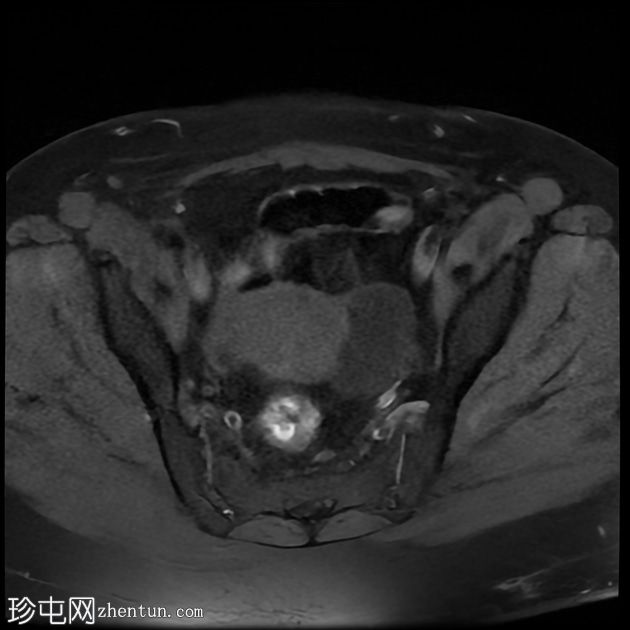

矢状位

T2加权像

左侧卵巢增大,呈弥漫性低T1信号和高T2信号,可见周边卵泡,部分卵泡除周边卵泡周围有环状强化外,无明显实质强化。左侧附件蒂呈漩涡状,提示卵巢扭转。